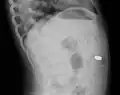

A coin seen on AP CXR in the esophagus -

A coin seen on lateral CXR in the esophagus -